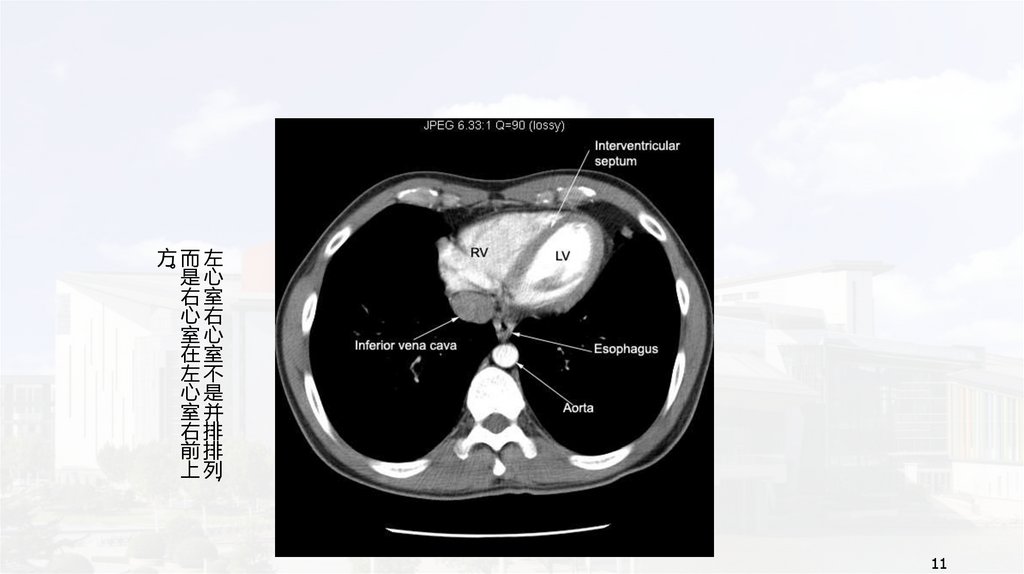

方而左

。是心

右室

心右

室心

在室

左不

心是

室并

右排

前排

上列

11